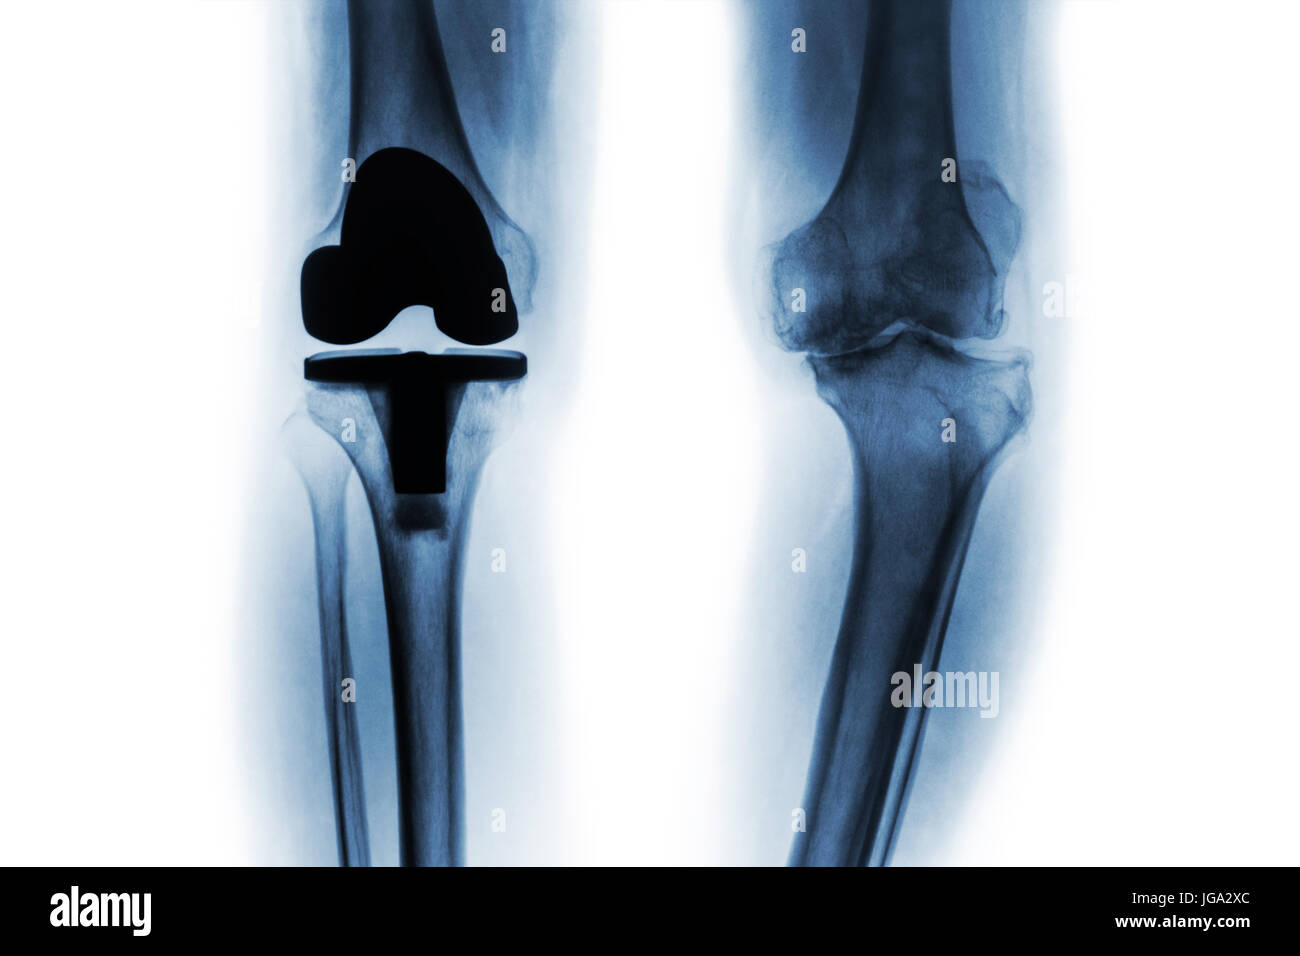

Film x-ray de l'arthrose du genou et patient articulation artificielle ( un remplacement total du genou ) . Fond isolé . Banque D'Imageshttps://www.alamyimages.fr/image-license-details/?v=1https://www.alamyimages.fr/photo-image-film-x-ray-de-l-arthrose-du-genou-et-patient-articulation-artificielle-un-remplacement-total-du-genou-fond-isole-147739277.html

Film x-ray de l'arthrose du genou et patient articulation artificielle ( un remplacement total du genou ) . Fond isolé . Banque D'Imageshttps://www.alamyimages.fr/image-license-details/?v=1https://www.alamyimages.fr/photo-image-film-x-ray-de-l-arthrose-du-genou-et-patient-articulation-artificielle-un-remplacement-total-du-genou-fond-isole-147739277.htmlRFJGA2XN–Film x-ray de l'arthrose du genou et patient articulation artificielle ( un remplacement total du genou ) . Fond isolé .

Film x-ray de l'arthrose du genou et patient articulation artificielle ( un remplacement total du genou ) . Fond isolé . Banque D'Imageshttps://www.alamyimages.fr/image-license-details/?v=1https://www.alamyimages.fr/photo-image-film-x-ray-de-l-arthrose-du-genou-et-patient-articulation-artificielle-un-remplacement-total-du-genou-fond-isole-147739284.html

Film x-ray de l'arthrose du genou et patient articulation artificielle ( un remplacement total du genou ) . Fond isolé . Banque D'Imageshttps://www.alamyimages.fr/image-license-details/?v=1https://www.alamyimages.fr/photo-image-film-x-ray-de-l-arthrose-du-genou-et-patient-articulation-artificielle-un-remplacement-total-du-genou-fond-isole-147739284.htmlRFJGA2Y0–Film x-ray de l'arthrose du genou et patient articulation artificielle ( un remplacement total du genou ) . Fond isolé .

Film x-ray de l'arthrose du genou et patient articulation artificielle ( un remplacement total du genou ) . Fond isolé . Banque D'Imageshttps://www.alamyimages.fr/image-license-details/?v=1https://www.alamyimages.fr/photo-image-film-x-ray-de-l-arthrose-du-genou-et-patient-articulation-artificielle-un-remplacement-total-du-genou-fond-isole-147739271.html

Film x-ray de l'arthrose du genou et patient articulation artificielle ( un remplacement total du genou ) . Fond isolé . Banque D'Imageshttps://www.alamyimages.fr/image-license-details/?v=1https://www.alamyimages.fr/photo-image-film-x-ray-de-l-arthrose-du-genou-et-patient-articulation-artificielle-un-remplacement-total-du-genou-fond-isole-147739271.htmlRFJGA2XF–Film x-ray de l'arthrose du genou et patient articulation artificielle ( un remplacement total du genou ) . Fond isolé .

Film x-ray de l'arthrose du genou et patient articulation artificielle ( un remplacement total du genou ) . Fond isolé . Banque D'Imageshttps://www.alamyimages.fr/image-license-details/?v=1https://www.alamyimages.fr/photo-image-film-x-ray-de-l-arthrose-du-genou-et-patient-articulation-artificielle-un-remplacement-total-du-genou-fond-isole-147739268.html

Film x-ray de l'arthrose du genou et patient articulation artificielle ( un remplacement total du genou ) . Fond isolé . Banque D'Imageshttps://www.alamyimages.fr/image-license-details/?v=1https://www.alamyimages.fr/photo-image-film-x-ray-de-l-arthrose-du-genou-et-patient-articulation-artificielle-un-remplacement-total-du-genou-fond-isole-147739268.htmlRFJGA2XC–Film x-ray de l'arthrose du genou et patient articulation artificielle ( un remplacement total du genou ) . Fond isolé .